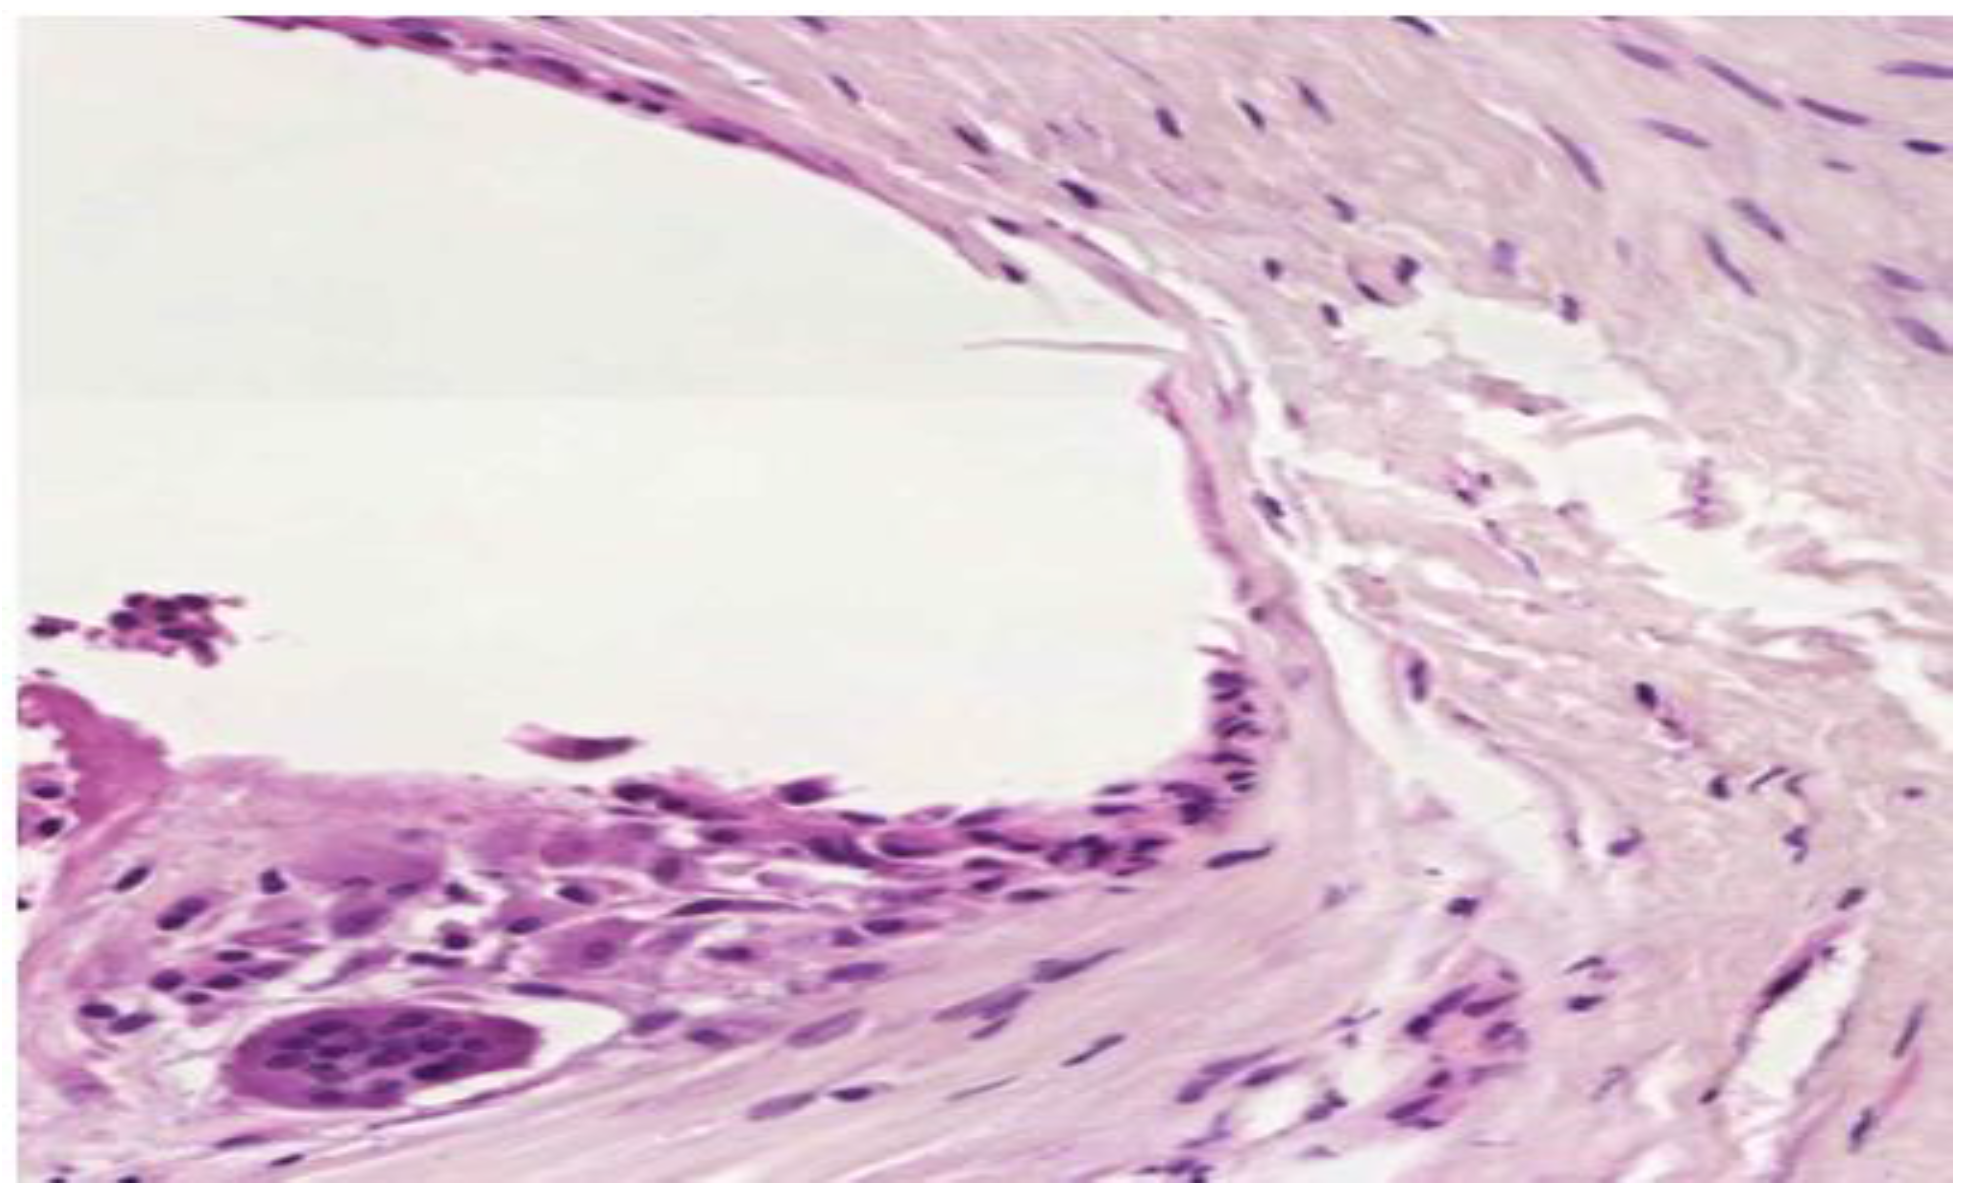

Fragments of well fitted but migrated alloplastic material presented fewer inflammatory cells, collagen fibers with increased diameter and a higher type I to type III collagen ratio (Figure 9).

Figure 9.

Low inflammatory infiltrate. Mature type I collagen with increased diameter. (H and E, ×10).